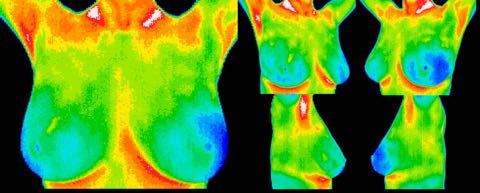

Early DCIS (ductal carcinoma in situ), age 30